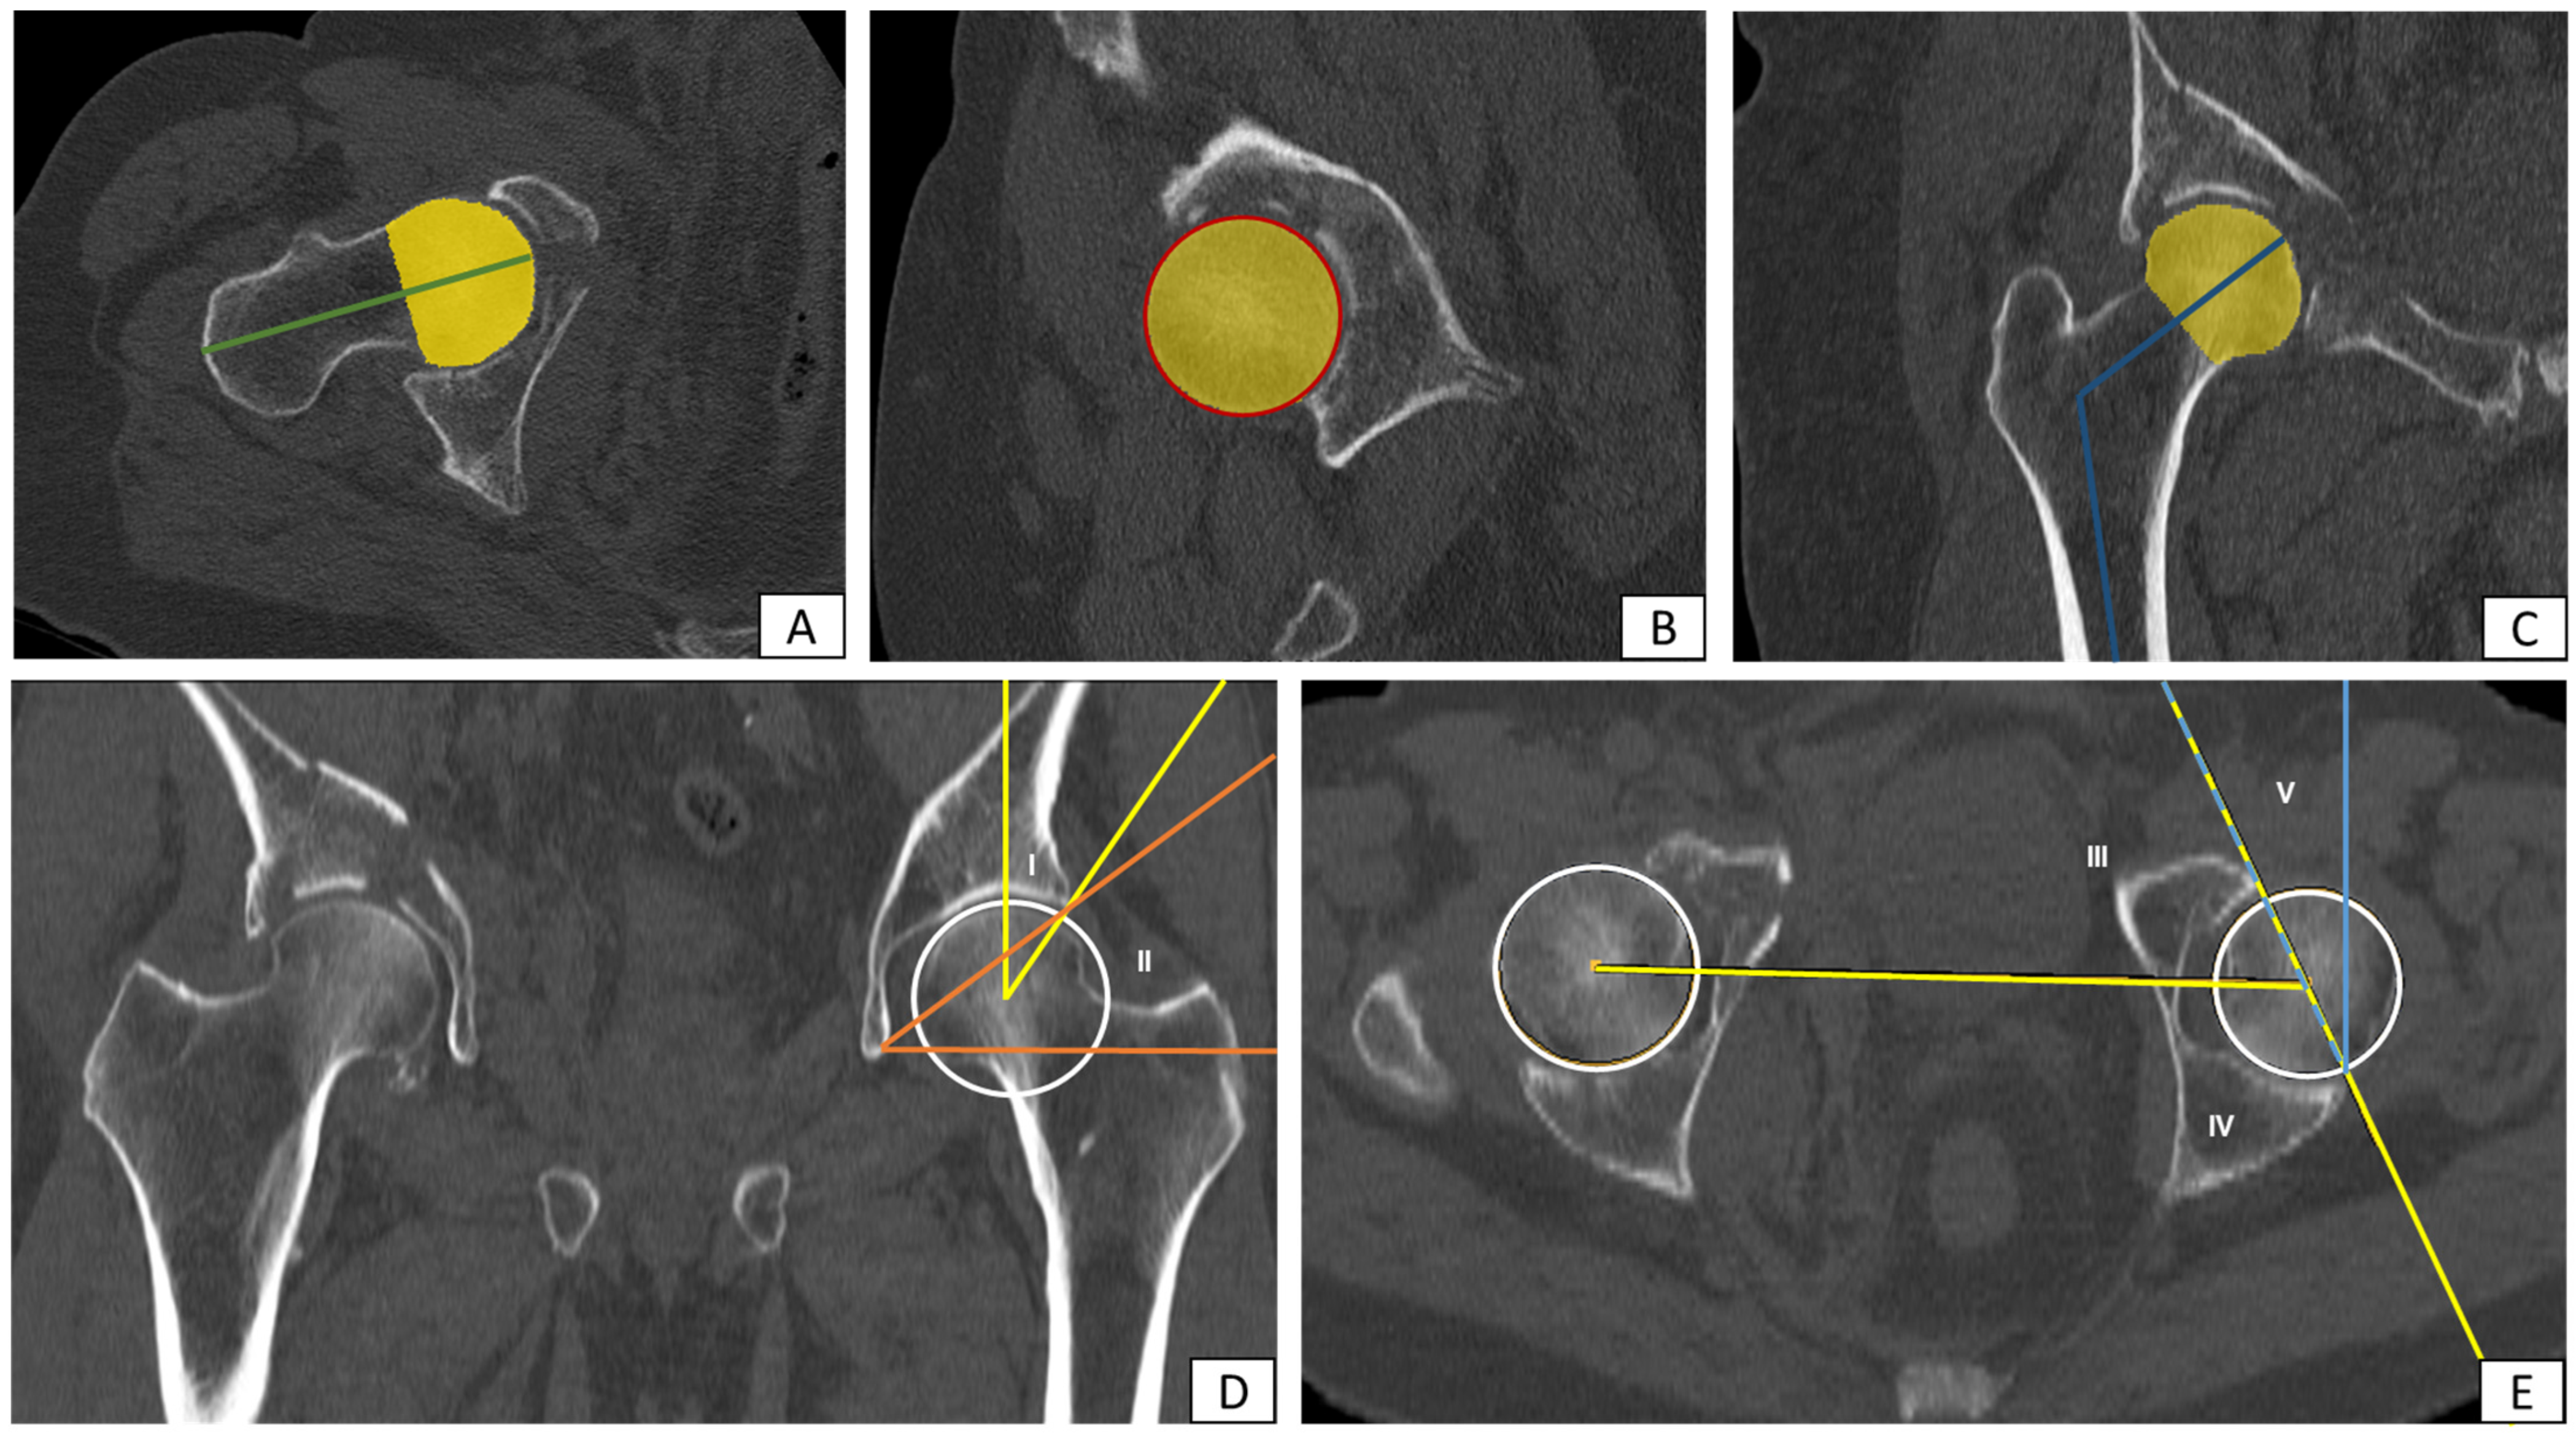

2.3. Measurement of Proximal Femur Geometry and Acetabular Geometry